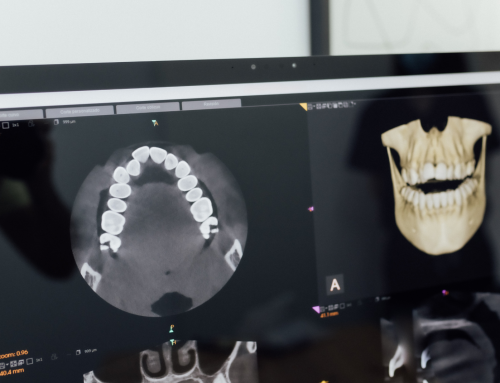

La elevación de seno maxilar es un procedimiento quirúrgico que se realiza en pacientes que necesitan someterse a un tratamiento de implantes dentales en la zona posterior del maxilar superior, especialmente cuando hay insuficiencia de hueso en esta área. Es comúnmente utilizada para pacientes que han perdido dientes en la parte superior de la boca y no tienen suficiente hueso para colocar los implantes de manera segura.

¿Qué es la Elevación de Seno Maxilar?

El seno maxilar es una cavidad ubicada en el maxilar superior, cerca de las raíces de los dientes posteriores. Cuando se pierden dientes en esta zona, el hueso en el área se reduce con el tiempo debido a la falta de estímulo que proporciona la raíz dental. Si la pérdida ósea es significativa, el espacio dentro del seno maxilar puede expandirse y acercarse al lugar donde se desea colocar el implante.

La elevación de seno maxilar consiste en levantar la membrana que recubre el seno maxilar para crear espacio y permitir que se coloque hueso artificial o natural (injerto óseo) en este espacio. Este injerto óseo servirá para estimular la regeneración de hueso nuevo y proporcionar una base sólida para los implantes dentales.

La elevación de seno maxilar es un procedimiento quirúrgico que se realiza en pacientes que desean someterse a un tratamiento de implantes dentales en la zona posterior del maxilar superior, especialmente cuando hay insuficiencia de hueso en esta área. Es comúnmente utilizada para pacientes que han perdido dientes en la parte superior de la boca y no tienen suficiente hueso para colocar los implantes de manera segura.

¿Qué es la Elevación de Seno Maxilar?

El seno maxilar es una cavidad ubicada en el maxilar superior, cerca de las raíces de los dientes posteriores. Cuando se pierden dientes en esta zona, el hueso en el área se reduce con el tiempo debido a la falta de estímulo que proporciona la raíz dental. Si la pérdida ósea es significativa, el espacio dentro del seno maxilar puede expandirse y acercarse al lugar donde se desea colocar el implante.

La elevación de seno maxilar consiste en levantar la membrana que recubre el seno maxilar para crear espacio y permitir que se coloque hueso artificial o natural (injerto óseo) en este espacio. Este injerto óseo servirá para estimular la regeneración de hueso nuevo y proporcionar una base sólida para los implantes dentales.

La elevación de seno maxilar es un procedimiento quirúrgico que se realiza en pacientes que desean someterse a un tratamiento de implantes dentales en la zona posterior del maxilar superior, especialmente cuando hay insuficiencia de hueso en esta área. Es comúnmente utilizada para pacientes que han perdido dientes en la parte superior de la boca y no tienen suficiente hueso para colocar los implantes de manera segura.

¿Qué es la Elevación de Seno Maxilar?

El seno maxilar es una cavidad ubicada en el maxilar superior, cerca de las raíces de los dientes posteriores. Cuando se pierden dientes en esta zona, el hueso en el área se reduce con el tiempo debido a la falta de estímulo que proporciona la raíz dental. Si la pérdida ósea es significativa, el espacio dentro del seno maxilar puede expandirse y acercarse al lugar donde se desea colocar el implante.

La elevación de seno maxilar consiste en levantar la membrana que recubre el seno maxilar para crear espacio y permitir que se coloque hueso artificial o natural (injerto óseo) en este espacio. Este injerto óseo servirá para estimular la regeneración de hueso nuevo y proporcionar una base sólida para los implantes dentales.